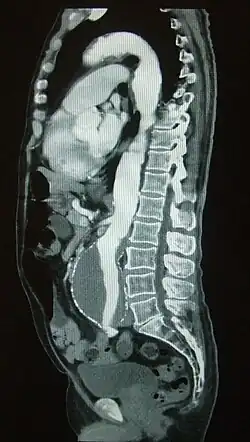

Sagittal CT image of an AAA